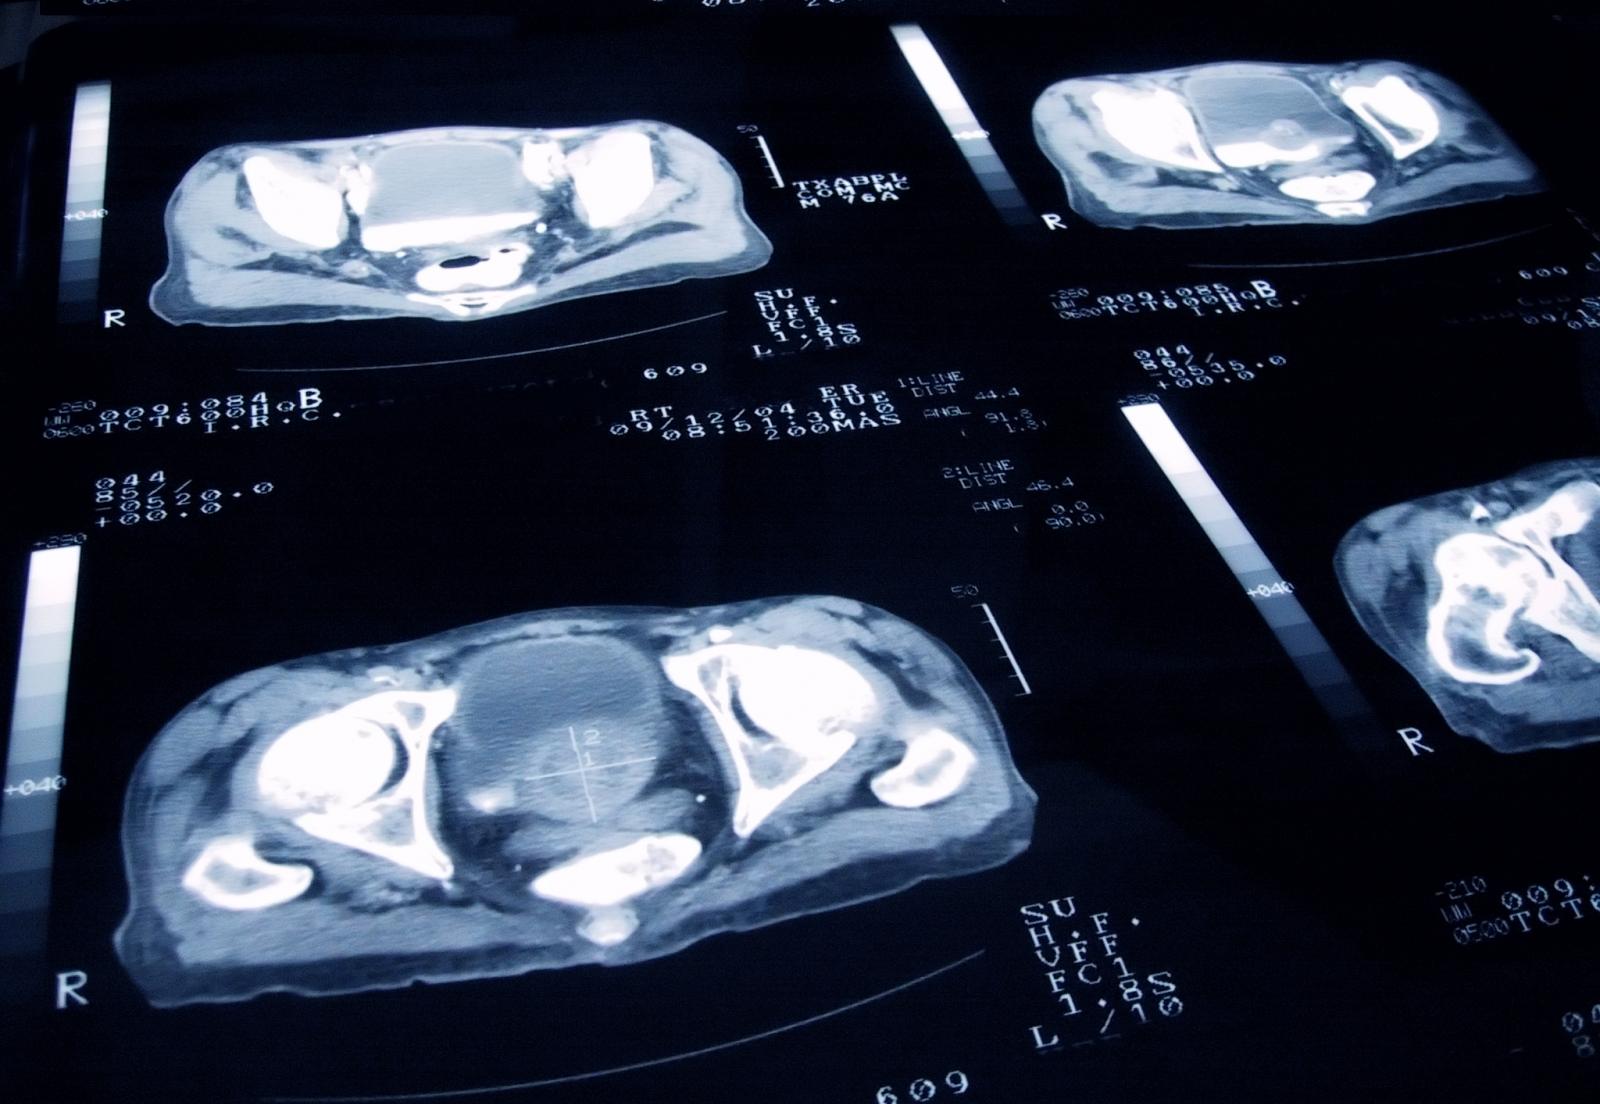

Image credit: iStock